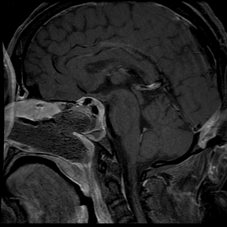

65 year old male with Pituitary Macroadenoma with cavernous sinus extension. Endoscopic Transsphenoidal Surgery done with Intraoperative MRI showing residual tumor in the cavernous sinus region under the left carotid artery. Post op MRI showing on the right no residual tumor in the sinus. (T1 contrast above and T2 coronal sections below).

- Pre-operative Coronal and Sagittal contrast enhanced T1W images show a well circumscribed homogenously enhancing sellar mass with suprasellar extension (Figure 1).

- Intra-operative coronal and sagittal T1W (Figure 2) contrast enhanced sequences show no residual enhancing tumour in the post operative bed (Figure 3).